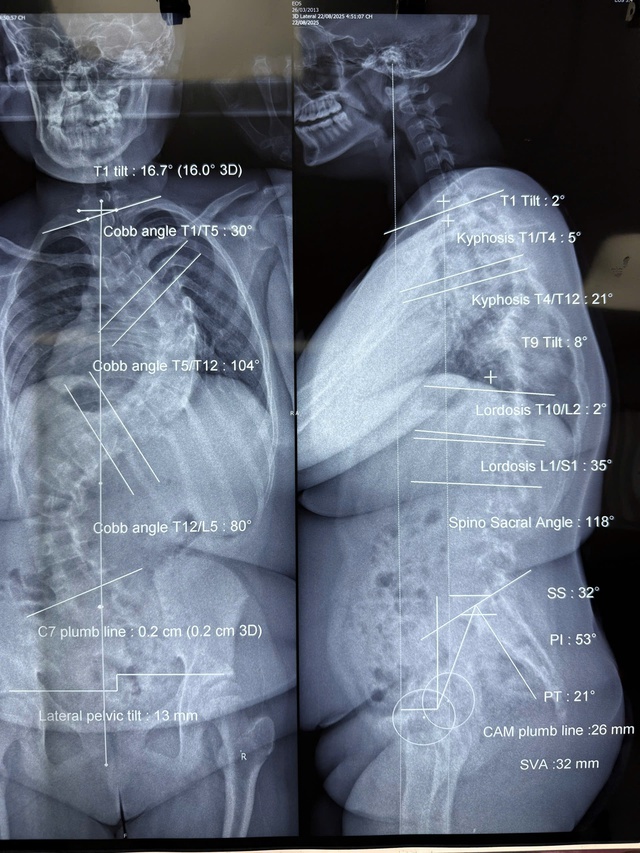

Trường hợp đầu tiên là bé M.N.C.L. (12 tuổi, ngụ huyện Hóc Môn). Tình trạng vẹo cột sống của bệnh nhi tiến triển nhanh bất thường. Tại thời điểm phẫu thuật, trẻ có hai đường cong lớn, trong đó đường cong chính vẹo 104 độ và đường cong thứ hai 80 độ. Trong 7 tháng chờ mổ, cấu trúc cột sống tiếp tục biến dạng nhanh và nặng.

Tình trạng cột sống của bệnh nhân M.N.C.L. trước khi phẫu thuật. Ảnh: BSCC.